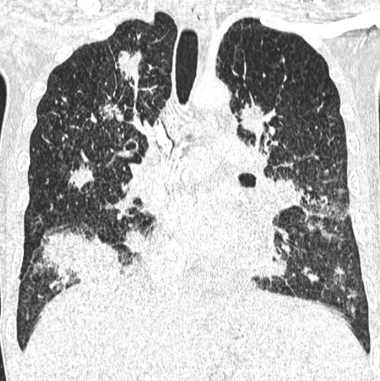

- Condensations nodulaires mal définies, “en flamme”

- Péribronchovasculaire

kaoposi aids sida vih hiv lung poumon poumons thorax thoracique sarcoma